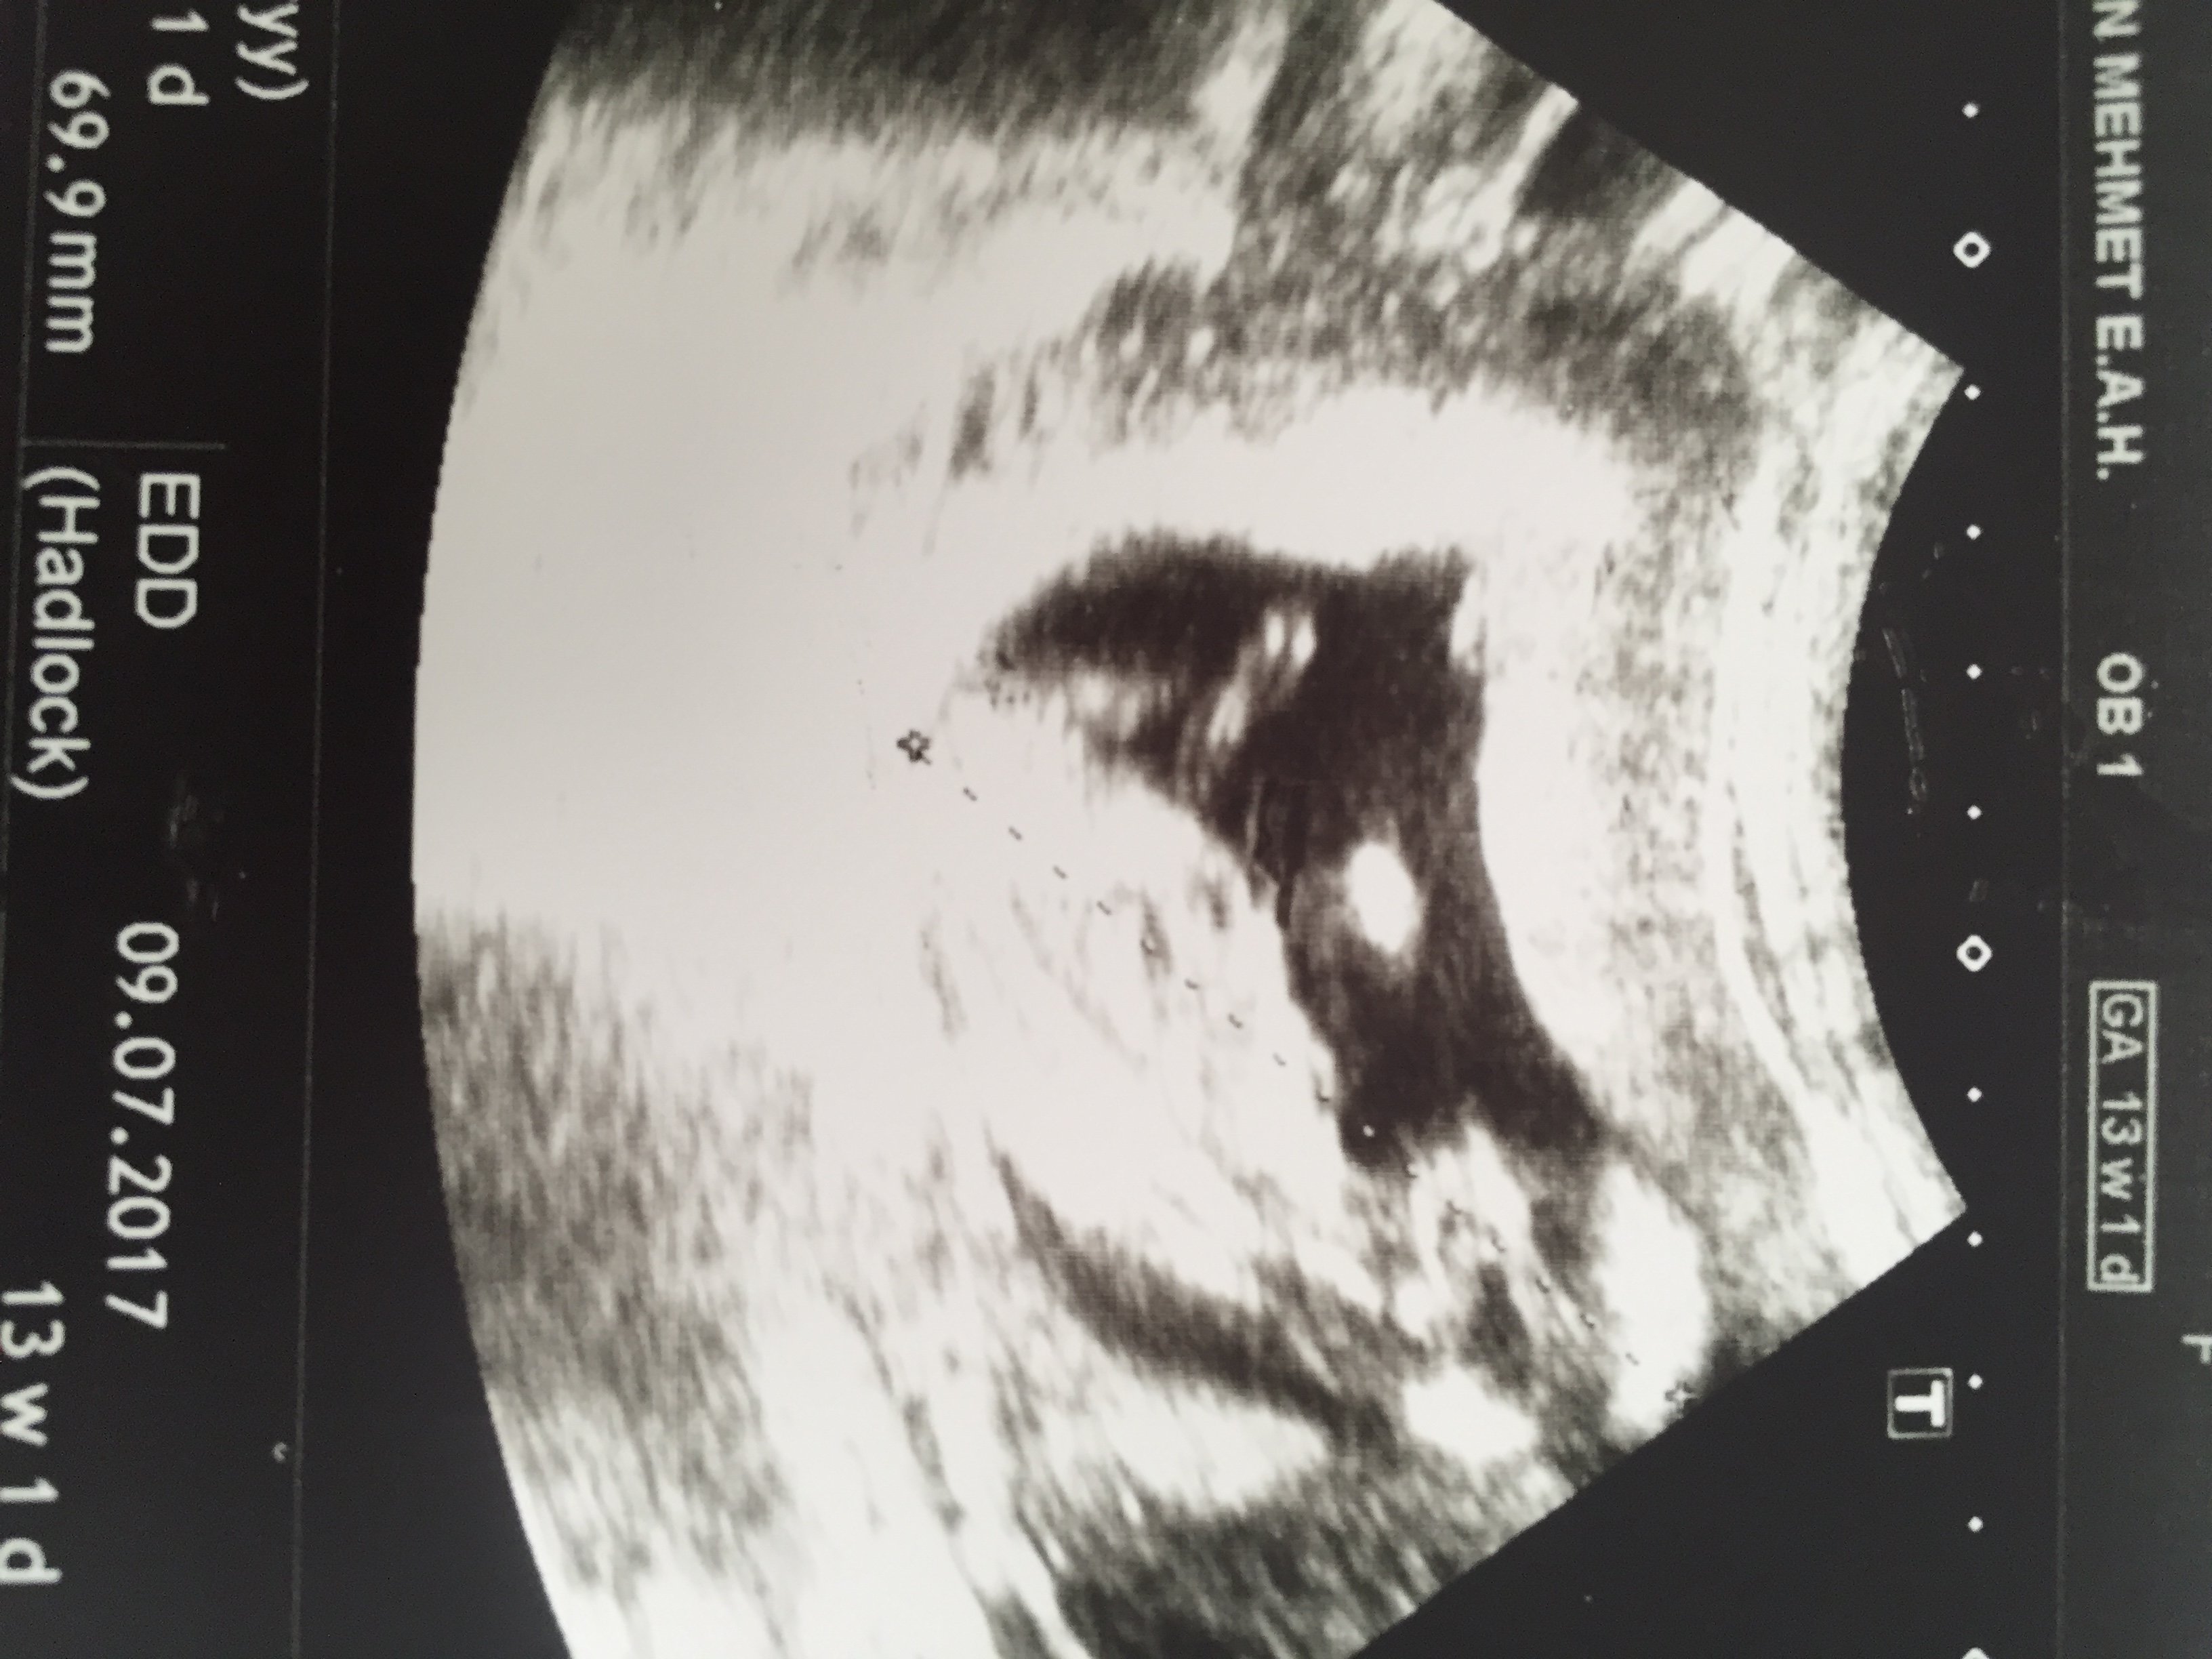

Bende bi tahmin alabilirmiyim mümkünse tabi ...

IMG_1083.JPG